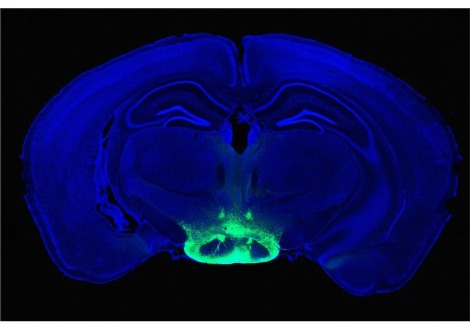

زاد النظام الغذائي عالي الدهون من الخلايا التائية الملتهبة وخفض عدد الخلايا التائية التنظيمية الملتهبة ( Tregs ) في الشريان الأبهر وهو أكبر وعاء دموي في الجسم والذي قام الباحثون بدراسته كمثال على ما كان يحدث داخل الأوعية الدموية عند الجنسين.

وجد الباحثون زيادة في الخلايا التائية في الكلى والتي تلعب دورًا رئيسيا في تنظيم ضغط الدم. تشجع هذه الخلايا الالتهاب عند كلا الجنسين ولكن كانت الزيادة الأكبر عند الذكور.